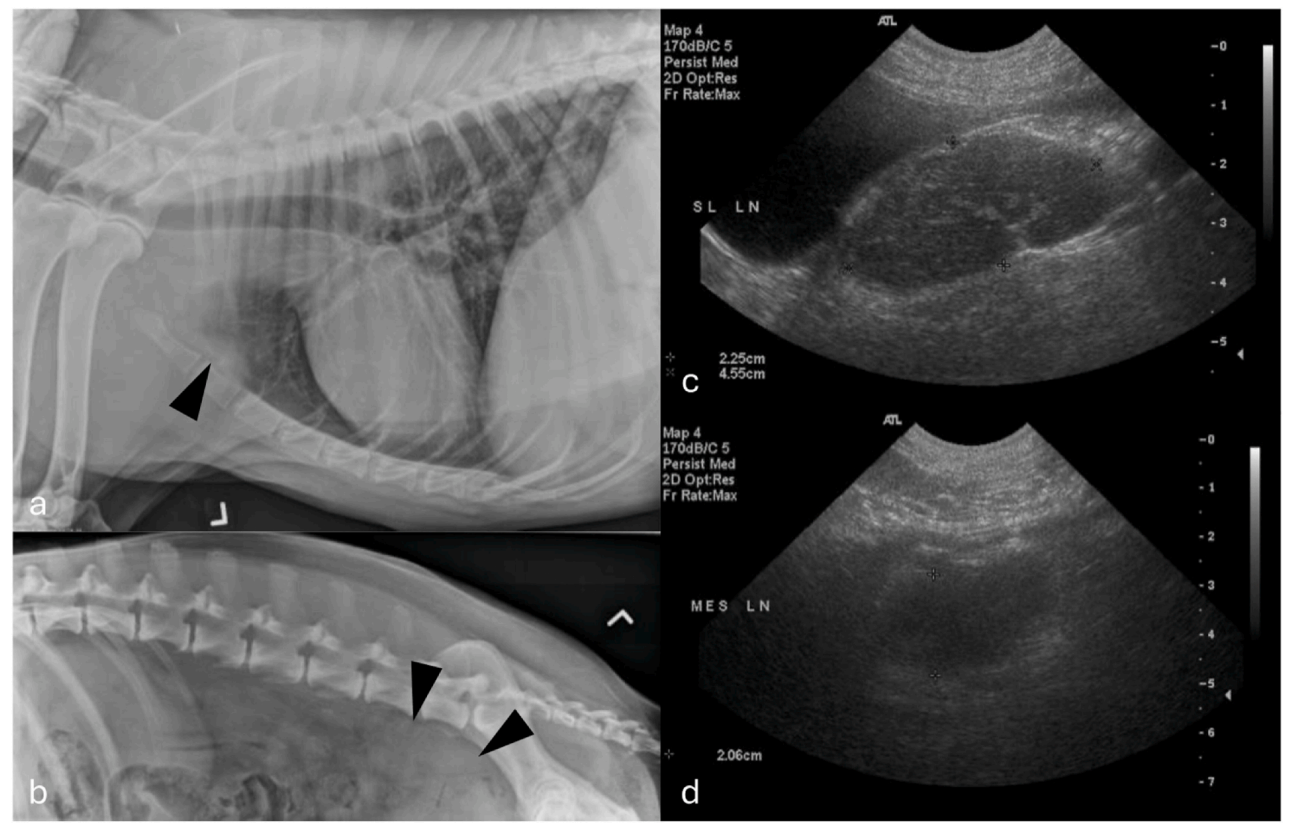

第236天,腹部超声和胸部X光检查(下图)证实了进行性多中心性淋巴结肿大,影响了腰下、肠系膜、下颌、腘窝、浅颈和胃淋巴结。还观察到肝脏肿大和脾脏肿大,伴有弥漫性网状结构;肝脏和脾脏的细胞学检查显示淋巴细胞性炎症和增生,并有髓外造血的证据。

↑ 胸部(a)和腰部(b)X光片显示胸骨淋巴结肿大,主支气管向腹侧偏移并呈扇形展开,肺门区域软组织不透明度增加,以及肝脏肿大。在颅侧腹膜后间隙发现一个大的圆形软组织不透明影,同时观察到腰下淋巴结肿大。腹部超声显示几乎所有可见的淋巴结,包括肠系膜(c)和腰下(d)淋巴结,中度至显著肿大,呈圆形,弥漫性且显著低回声,直径大小从1厘米到大于2.5厘米不等。